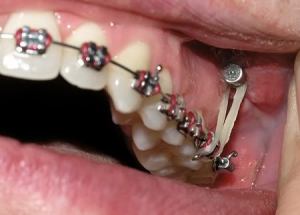

A bone screw anchor. Ouch. Looks painful! Here’s another example on a model set of teeth rather than a gross mouth:

This would be installed to raise my upper molars so they don’t clash with the lower molars once they are fully in position.